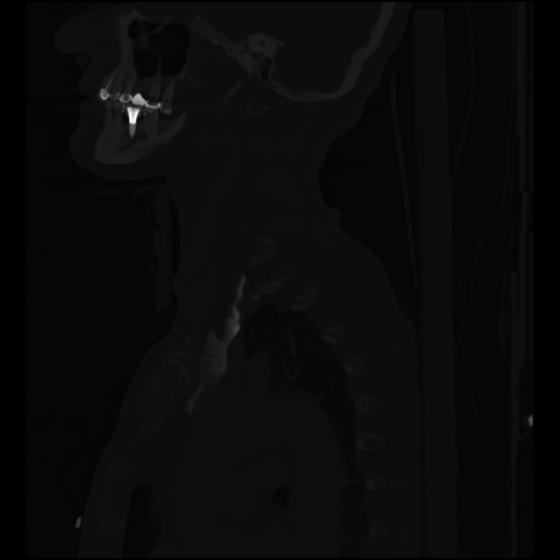

24 ANGIO,CE,Sag-MIP,5.000,ANGIO,Sag-MIP,